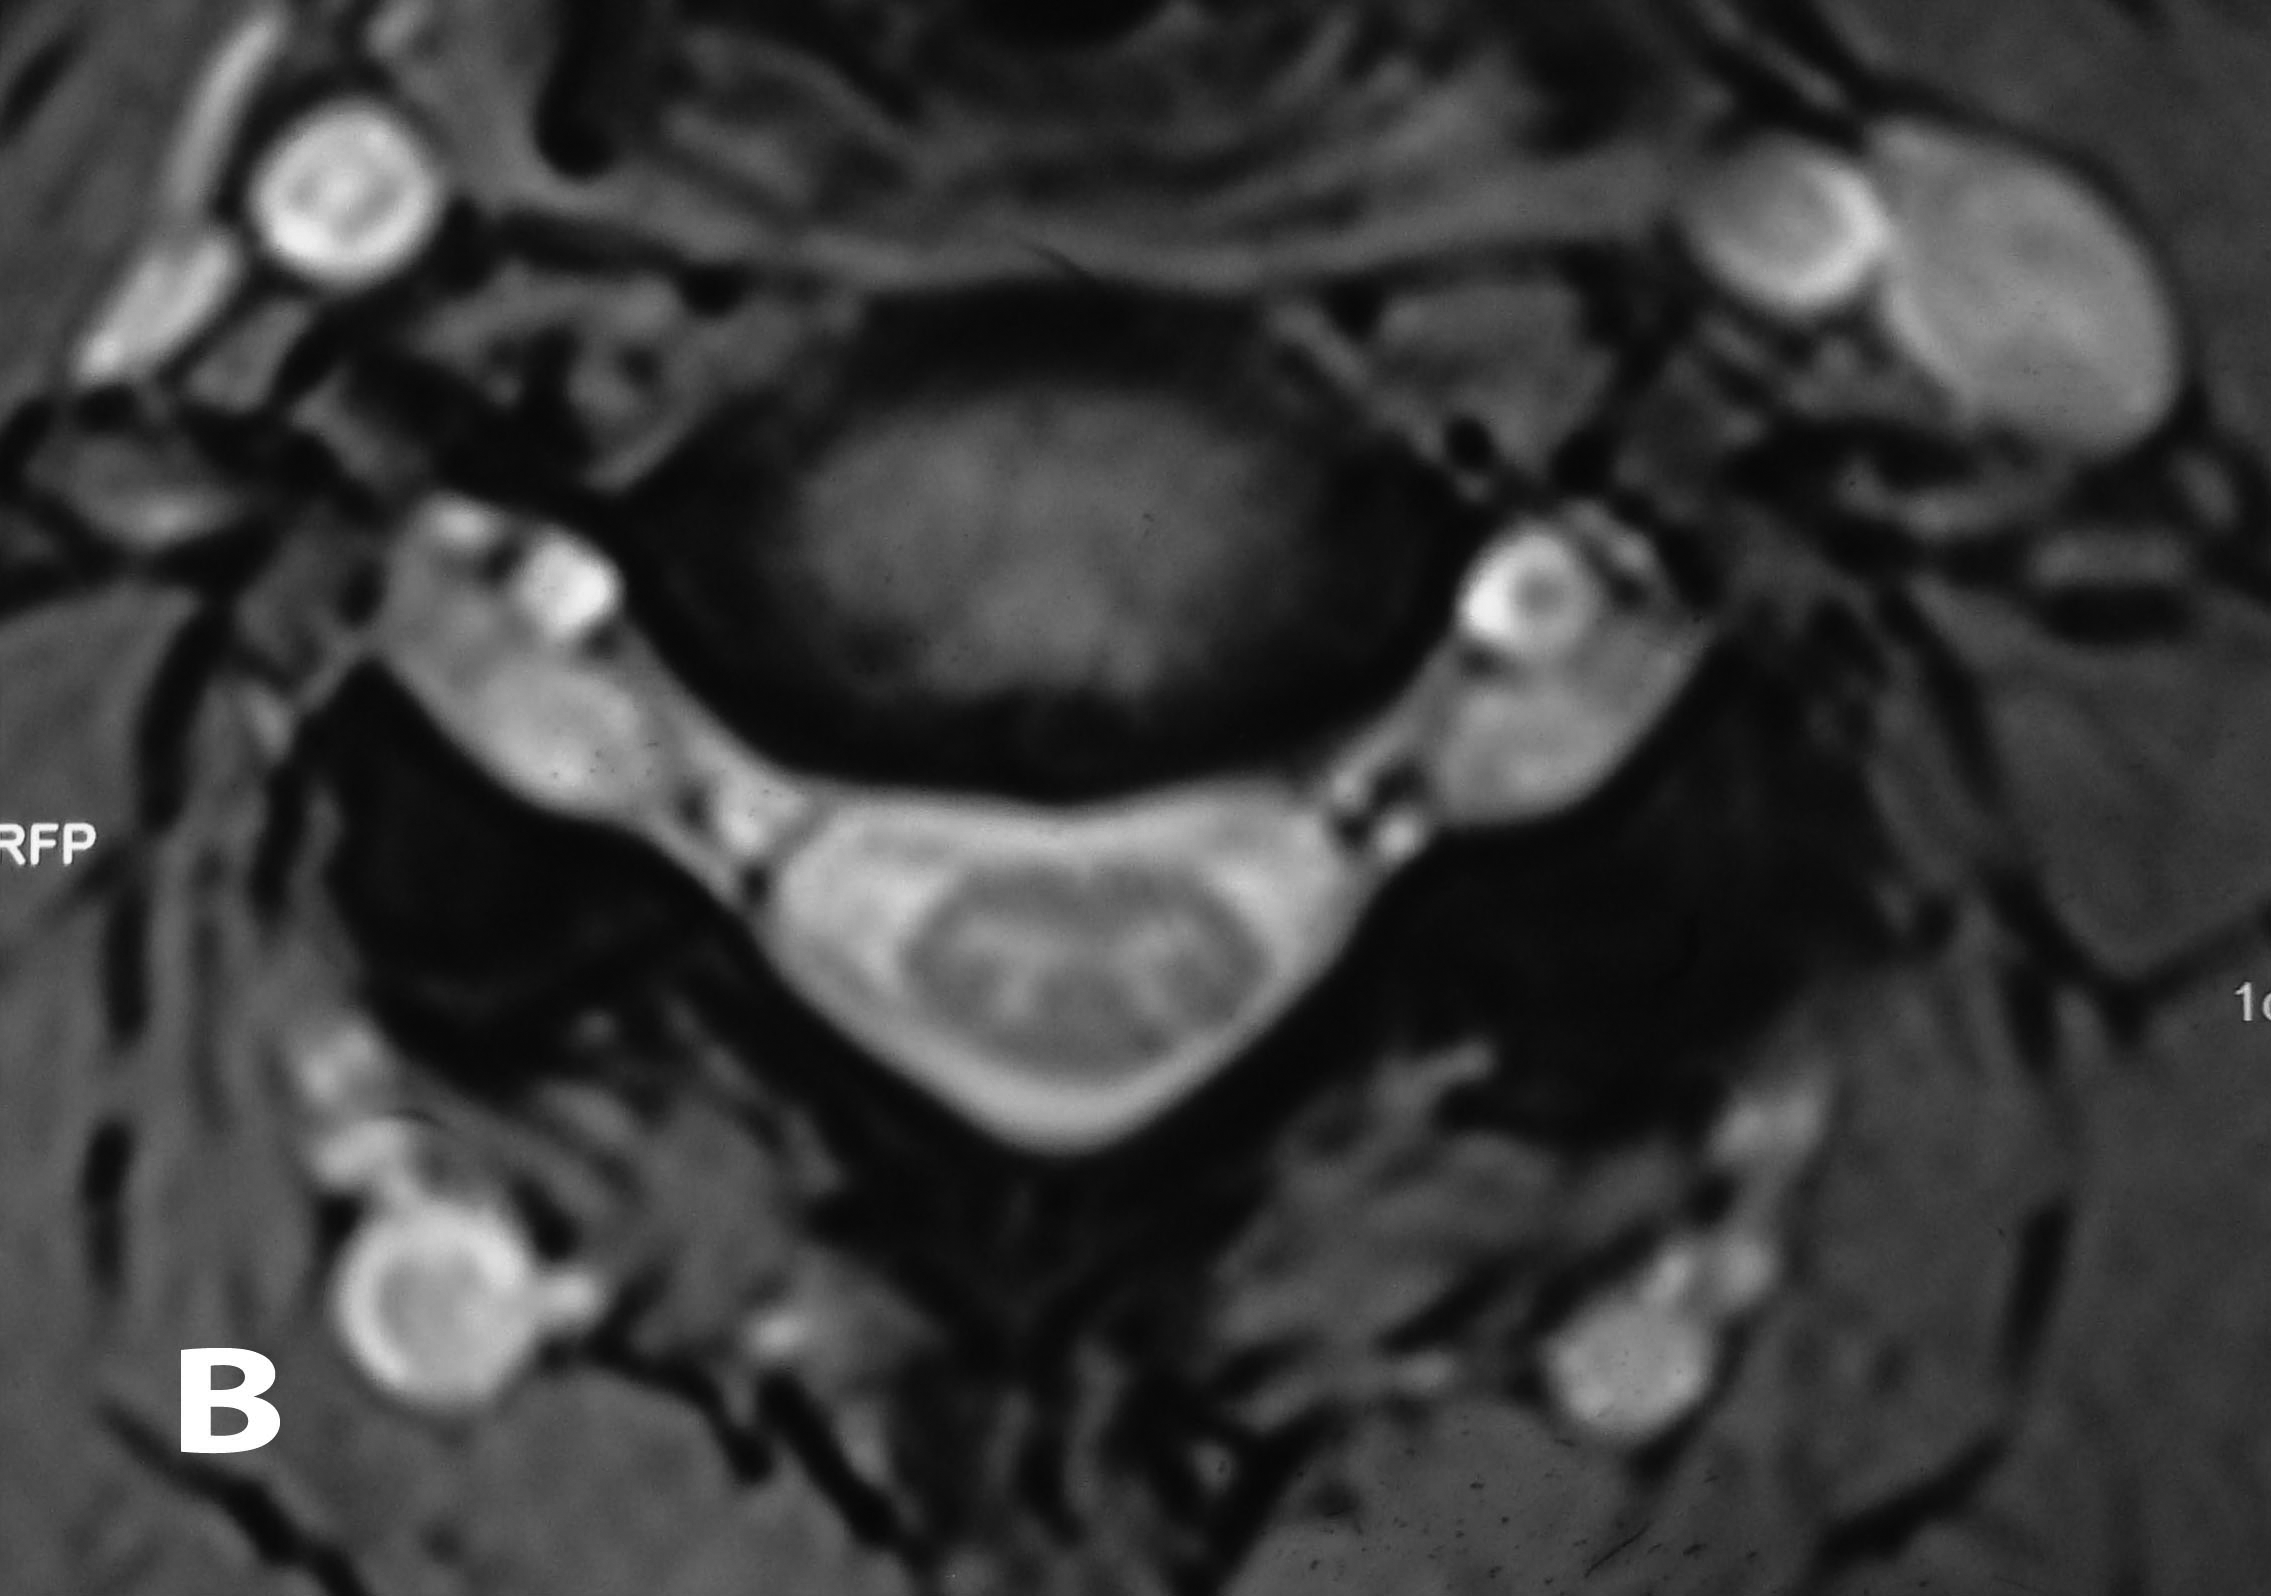

Plain radiographs showed no abnormalities. MRI of the cervical spine was done. Sagittal T2W images showed hyperintense lesion at both C5-C6 neural foramen (Figure 1 & 2). Axial T2W images showed bilateral cervical perineural cyst at C5-C6 neural foraminae (Figure 3A & 3B). Post-contrast study showed no abnormal enhancement along the cysts. EMG-NC studies showed evidence of C5C6 chronic motor axon degeneration at root level. Left deltoid and biceps showed high amplitude large duration motor unit potentials during voluntary activity.

Figure 3A & B Axial T2W images of the cervical spine demonstrating bilateral cervical perineural cyst at the C5-C6 level.